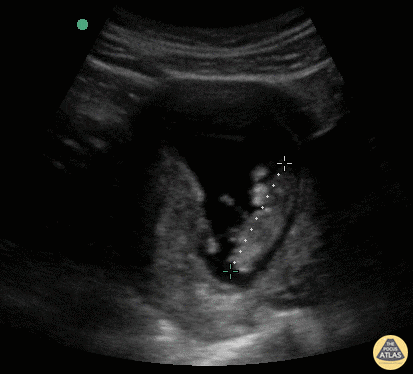

OB Dating Atlas - Week 10 - Crown Rump Length (CRL)

A 24-year-old G0 with an unknown LMP presents for a missed period and confirmation of pregnancy. She had a positive UPT 5 days ago. On abdominal ultrasound, an embryo is visualized. The crown-rump length measures 3.84 cm consistent with a 10w5d IUP. General Rules: Most accurate single measurement once the embryo is present (6w0d-13w6d) [1] Mean of 3 linear measurements from the outer margin of the cranium/cephalic pole to caudal rump in the true midsagittal plane. Gestational Age (weeks) = CRL (cm) + 6.5 This equation can be used when using a portable or handheld device that does not auto calculate the gestational age. Accuracy3: ± 5 - 7 days